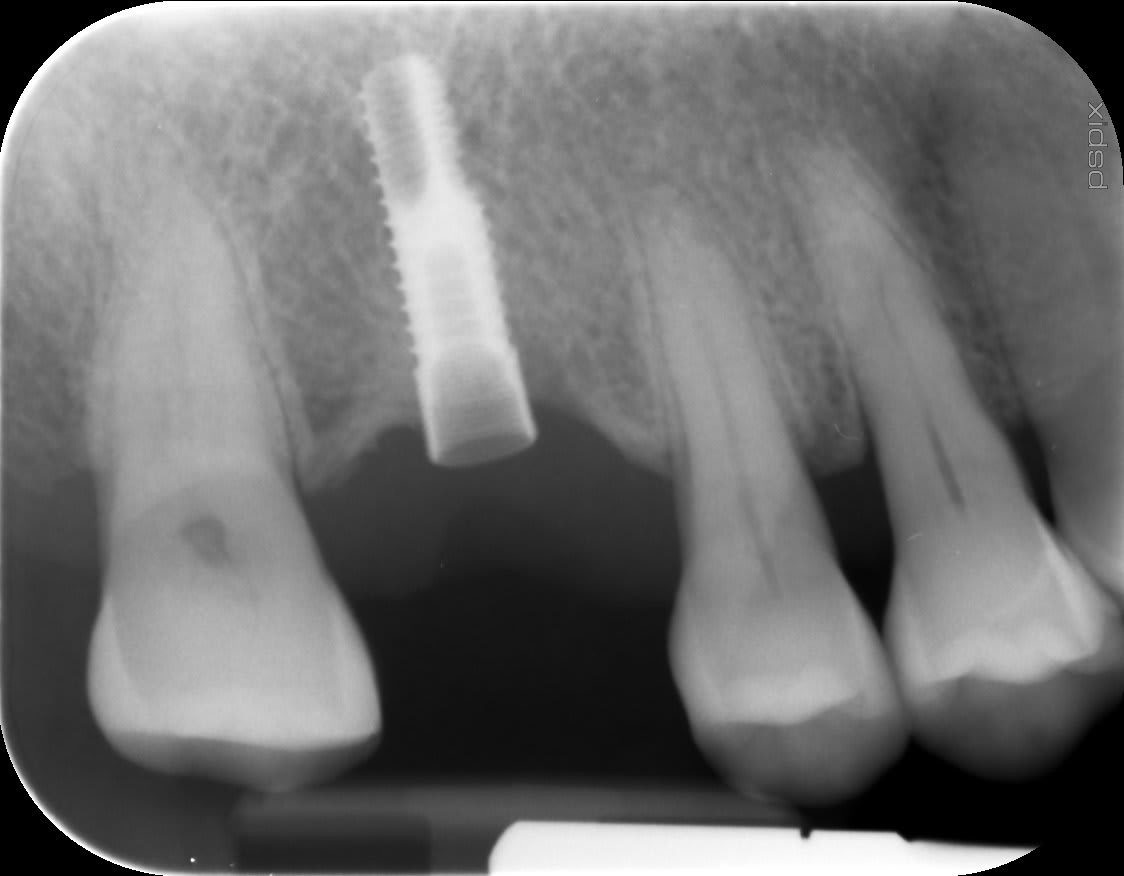

Sauriez-vous identifier l'implant présent sur cette radiographie rétroalvéolaire?

Radio pour ainsi dire inexploitable....trop pixelisée, je n'arrive pas à déterminer la forme des spires ni s'il y a des microspires au col.....

J'ai reposté une 2e photo de la radiographie, est-ce que vous pensez pouvoir mieux identifier l'implant?

non, photo au smartphone de l'écran = plein de pixels, ça ne vaut rien

il faut faire un export en jpeg du logiciel d'imagerie et poster sur nonol

Voilà c'est fait, j'ai reposté la RX.

Voilà c’est tout de suite mieux

https://www.spotimplant.com/fr/implants-dentaire/etk/natea-classic